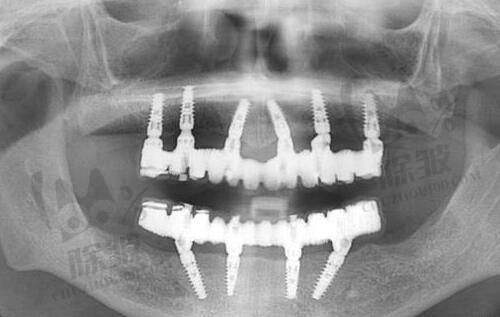

窦云轲医生擅长植发,阳医生擅长牙齿矫正。